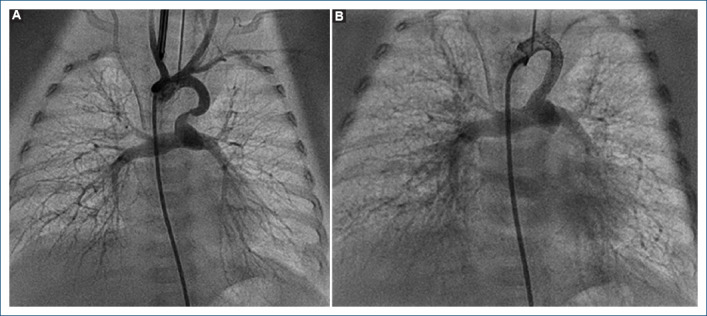

Abstract Image